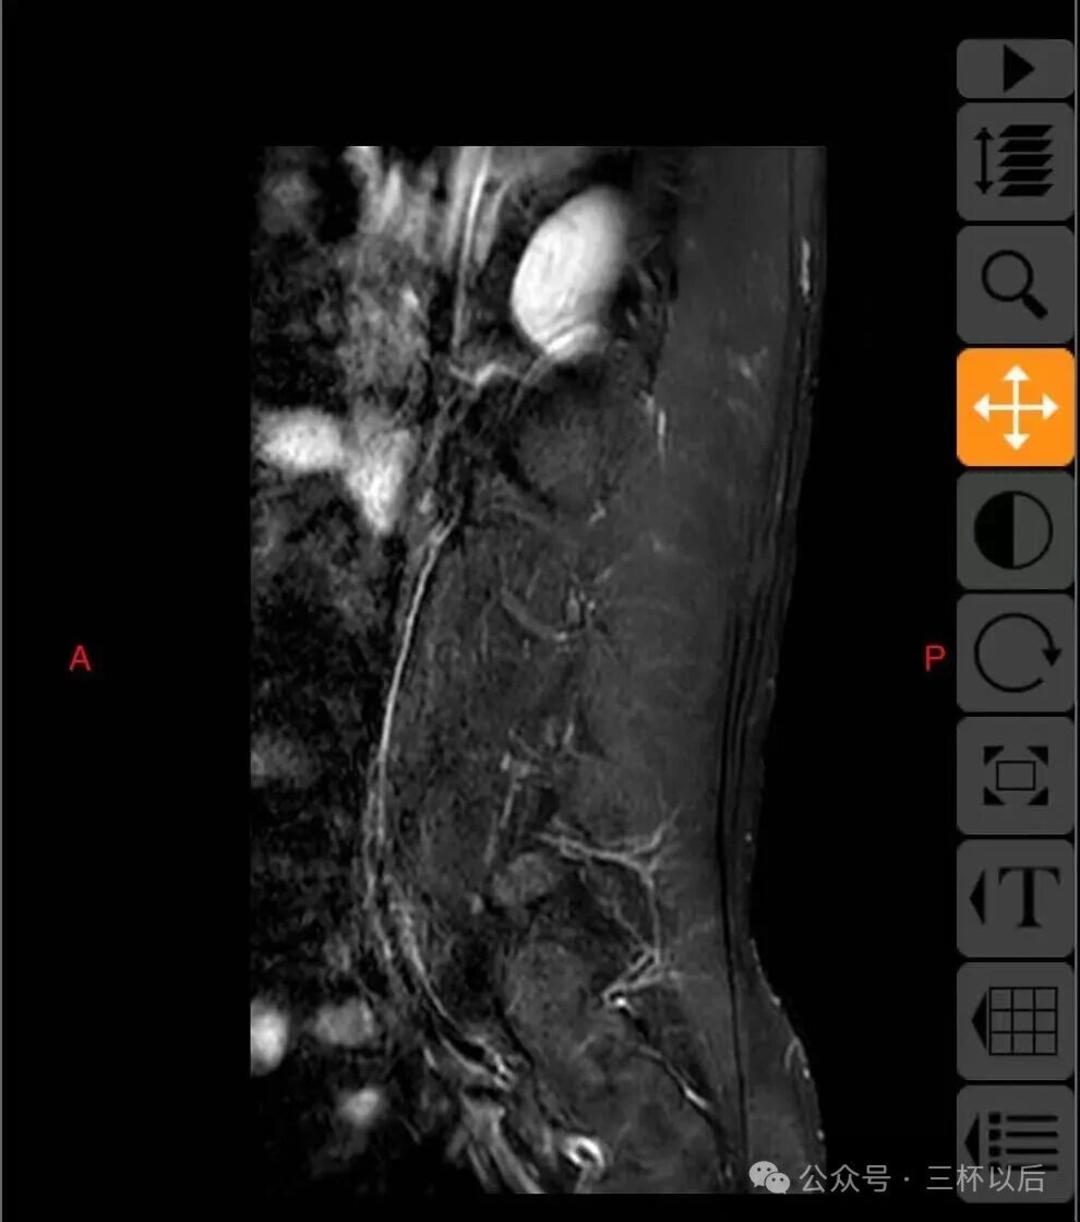

顺便贴一下拍的片子,如果有懂行的欢迎给我建议,我听劝的。真真希望能恢复如初,现在每天都能感受到疼痛,用了各种办法也不管用。